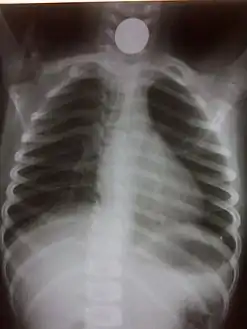

If the person who swallowed the foreign body is doing well, usually an x-ray image will be taken which will show any metal objects, and this will be repeated a few days later to confirm that the object has passed all the way through the digestive system. Also it needs to be confirmed that the object is not stuck in the airways, in the bronchial tree.

- Chest radiograph showing a Venezuelan 25 cent coin lodged in the upper esophagus of a 9-year-old girl.

- A coin seen on AP CXR in the esophagus